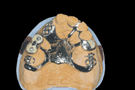

deux implants et attachements oring pour aider a la retention d'une plaque a édentation bilatérale apres la 22, et la 14 c'est casse gueule?

annie Ecrivait:

-------------------------------------------------------

> deux implants et attachements oring pour aider a

> la retention d'une plaque a édentation bilatérale

> apres la 22, et la 14 c'est casse gueule?

plutot si prothèse rigide ....